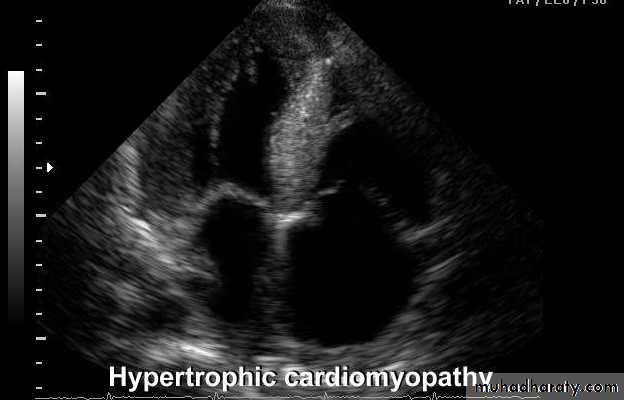

This is the most common form of cardiomyopathyGenetic disorder, usually with autosomal dominant transmission

• Hypertrophic cardiomyopathy

Types

Obstructive 25 %

Non obstructive

The hypertrophy may be generalised or confined largely to the interventricular septum (asymmetric septal hypertrophy or other regions (e.g. apical hypertrophic cardiomyopathy)

ECHO Echocardiography is diagnostic

Cardiovascular Diseases